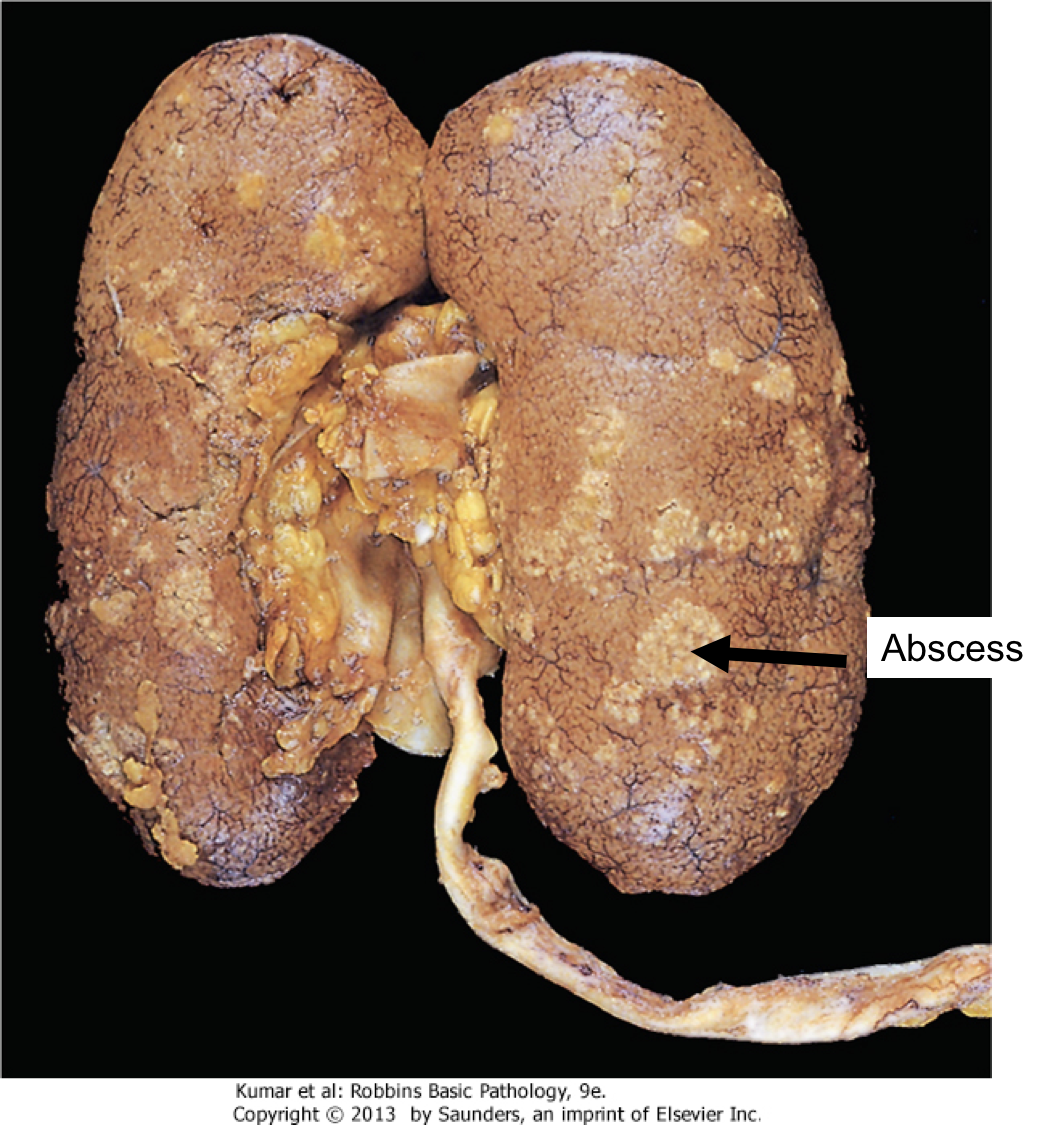

What is wrong with it? (this is one kidney cut in half and opened like a book, but we are seeing the capsular portion)

This is a fixed kidney demonstrating acute pyelonephritis

What in God’s name is going on here?

The inside of a kidney demonstrating acute pyelonephritis